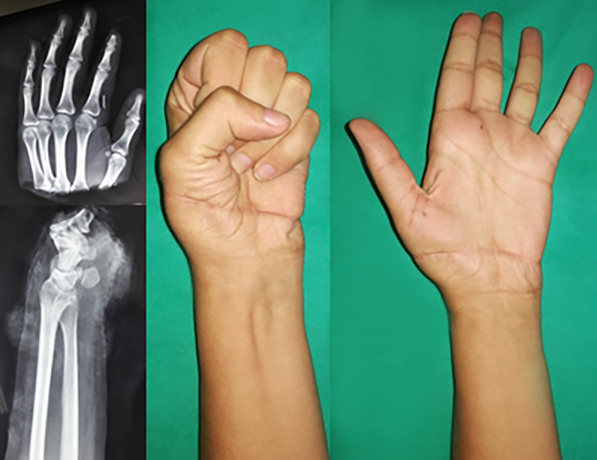

levo: Muškarac 52 godine replantacija palca 7 nedelja posle operacije.

desno: Replantacija šake – spoljašnja fixacija kosti ProFix aparat |